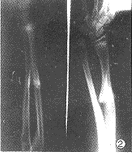

临床放射学杂志001226 例1 女,22岁。左桡骨远端及左股骨下端各有一肿物7年,呈渐进性增大。体检见左腕部及左股骨下段各有一肿块,质硬,无压痛。X线片示:左桡骨远端距腕关节面约3cm处向尺侧生长一骨性肿物,压迫尺骨。左尺骨发育短小,远端变形,桡骨弯曲凸向外侧,侧位片见尺骨指向后方,下尺桡关节脱位,近排腕骨排列失去正常自然弧度,形成以月骨为中心锥形排列。X线诊断:多发性骨软骨瘤继发假性Madelung畸形(图1)。术后病理报告:骨软骨瘤。

例2 女,14岁。右前臂中段出现一肿物10年,渐增大,质硬,无压痛。X线片示:右桡骨中段有一骨性突起,右桡骨变短稍弯曲,其远端骨骺内侧发育较小,尺骨相对较长,下尺桡关节半脱位。腕骨失去正常排列,腕骨角变小,形成以月骨为中心锥形排列。X线诊断:右桡骨中段骨软骨瘤并发假性Madelung畸形(图2)。术后病理诊断:骨软骨瘤。

图1 左桡骨远端骨软骨瘤,桡骨弯曲,左尺骨短小,远端变形,下尺桡关节脱位,腕骨排列失常,形成以月骨为中心锥形排列图2 右桡骨中段骨软骨瘤,其远端骨骺内侧发育较小,下尺桡关节半脱位,腕骨角变小,形成以月骨为中心锥形排列 图3 右尺骨骨软骨瘤,尺桡骨弯曲,尺骨发育短小,下尺桡关节脱位,腕骨发育迟缓